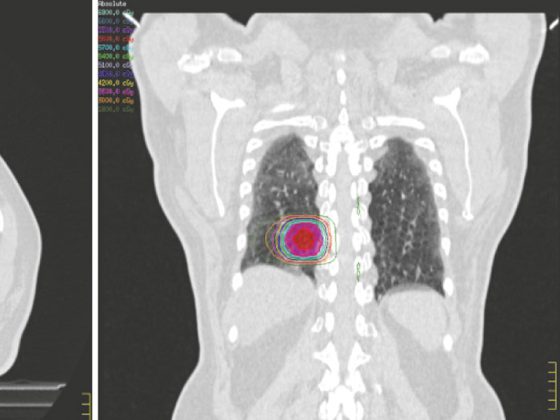

• Nicht-kleinzelliger Lungenkrebs (NSCLC)

Aktuelle Konzepte der Strahlentherapie

• Fortbildung

• Onkologie

• Pneumologie

• Radiologie

• Rx

Weiterlesen